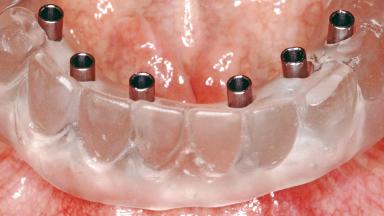

Conventional Loading of Six Implants in the Mandible and Final Restoration with a Full-Arch Metal-Ceramic FDP

# of Implants 6

Type of Implants One-Piece

Loading Protocol Conventional/early

Retention Screw-retained, with 4 or more splinted implants Screw-retained, with 4 or more splinted implants